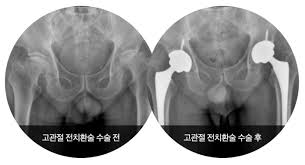

- 고관절 전치환술(Total Hip Arthroplasty, THA): 골관절염이나 류마티스 관절염, 골절 등에 널리 사용되는 방식으로, 관절 전체를 인공 관절로 교체합니다.